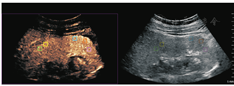

选取两组肾脏各5个感兴趣区域,每个ROI区域为正方形5 mm×5 mm选择框,选取注药后1 min图像,对其进行动态分析研究,应用QLAB软件,绘制肾皮质TIC曲线。对照组TIC曲线上升陡直,迅速达到峰值强度,而后缓慢下降至基础水平,见图2。实验组TIC曲线上升平缓,达到峰值强度延迟,下降缓慢,且峰值强度较低,造影剂消退较对照组快,见图3。

CEUS目前已被广泛用于肾脏疾病,包括膀胱输尿管反流、糖尿病性肾脏疾病(diabetic kidney disease,DKD)、复杂性囊肿、肾脏肿瘤、慢性肾脏疾病(chronic kidney disease,CKD)、缺血性肾脏疾病和肾脏移植等肾脏病变随访,尚无研究评价CEUS对UPJO肾脏功能评估的有效性[14]。灌注参数中,TTP指超声造影剂开始进入感兴趣区肾皮质至达到强度峰值的时间,PI是指造影剂在一定时间内达到的最强信号强度,A指TIC曲线的上升支斜率,反映了肾皮质在血流灌注时血流速度和密度随时间的变化情况。AUC指一定时间内TIC曲线下面积,与微泡分布容积、血流速度及灌注时间有关,本研究截取注入造影剂后1min内的血流灌注情况,绘制TIC曲线。实验组TIC曲线上升平缓,达到峰值强度延迟,下降缓慢,且峰值强度较低。肾功能发生损害时,功能性肾血管收缩和全身血管扩张,导致血管阻力增加,肾脏皮质的灌注减低,单位时间的微泡容积减少,TIC曲线上升平缓。对照组和实验组的肾皮质血流灌注CEUS图像表明TIC可以通过肾灌注改变评价肾脏功能。